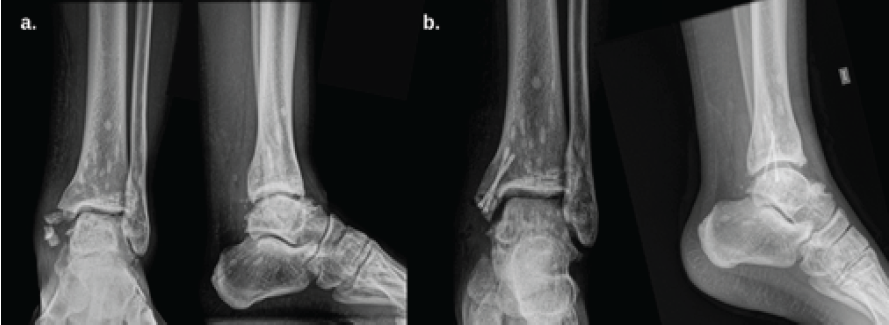

A 21-year-old male with no significant medical history experienced a twisting injury to the left ankle, resulting in pain, bruising, and swelling, without skin breakage or neurovascular compromise. He presented to the emergency department, where anteroposterior, lateral, and mortise ankle X-rays and a computed tomography (CT) scan revealed a comminuted and displaced medial malleolus fracture and avulsion fracture of the lateral process of the talus. In addition, multiple small (2–16 mm), punctate, well-defined, round and oval-shaped sclerotic lesions were found symmetrically in the distal left tibia, fibula, and talus (Fig. 1a and b), sparing the joint space and without affecting bone architecture or soft tissues.

Figure 1: (a): Pre-op anteroposterior (AP) and lateral X-rays of the left ankle showing multiple small (2–10 mm), well-defined, oval-shaped sclerotic lesions symmetrically distributed in the distal tibia, fibula, and talus, with no cortical disruption or periosteal reaction. A comminuted medial malleolus fracture is also visible. (b): Post-op AP and lateral X-rays showing the same sclerotic lesions and a fixed medial malleolus fracture with two cannulated screws.

Surgery involved an open reduction of the medial malleolus through a medial ankle approach. The sagittal fracture line was stabilized temporarily with a Kirschner wire, and definitive fixation was achieved with two 2.5 mm headless cannulated compression screws (38 mm and 35 mm in length) (Fig. 1b). One-month post-op, the patient began physiotherapy, walking without complications, and ascending/descending stairs without issues. He reported only occasional pain, Visual Analog Scale 2/10 when walking on uneven surfaces. He returned to work as a fisherman 5 weeks after surgery. After completing physical therapy, follow-up was periodic. At his last check-up, 17-month post-op, he had no pain or complaints and exhibited normal function (neutral dorsiflexion and 60° plantar flexion).